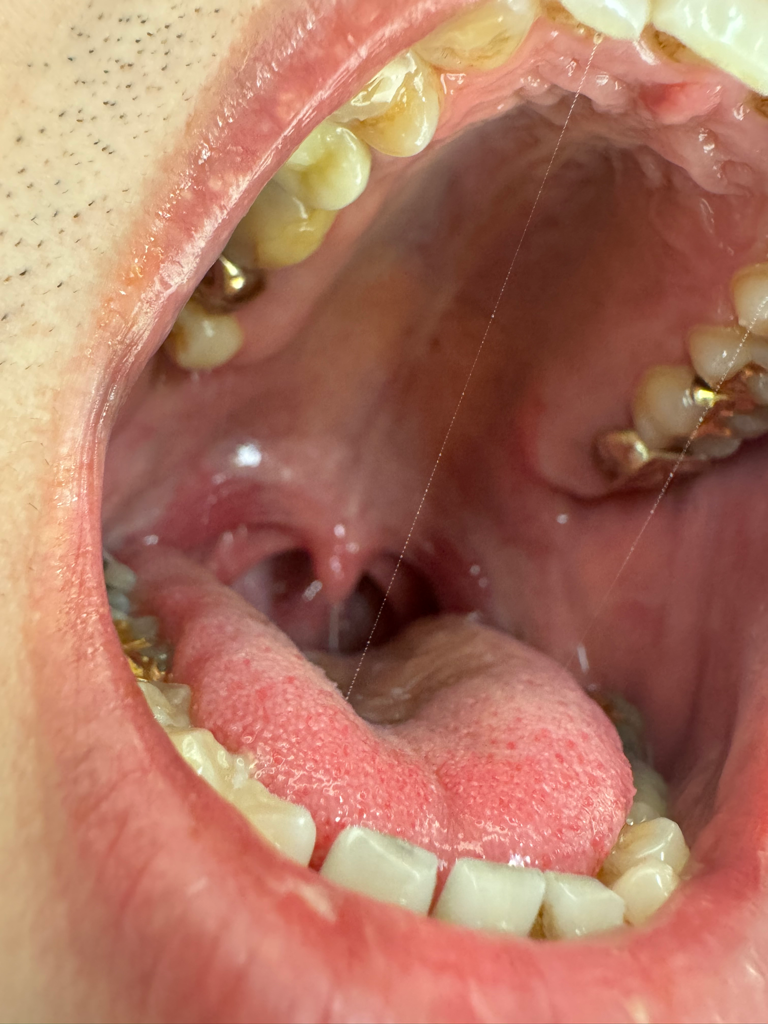

구강 내에 보면 볼 안쪽.. 그러니까 어금니쪽 부위와 맞닿아있는 볼 안쪽 점막이 건조하다고 해야하나 얼얼하다고 해야하나 그런 느낌이 있습니다

(뭐가 돌출 되어 있거나 그런 증상은 없습니다)

하얀 일직선의 선이 있기는 합니다..

사진이 잘 안보일 수 있긴한데.. 저의 이런 임상증상이나 사진으로만 보면 제가 구강암까지 걱정해야하는 것일까요?

사진만 봐서는 특별한 이상도 없다고 판단되고, 증상으로도 구강암을 의심할 수 있는 상태는 아닌 듯 싶습니다.